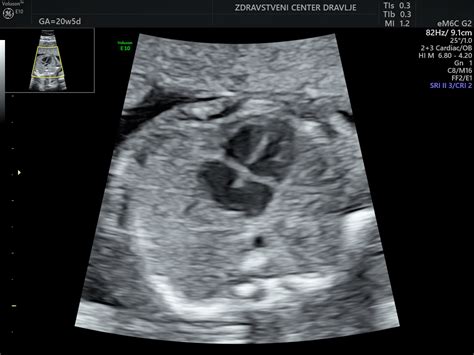

Med 19. in 23. tednom nosečnosti sledi morfologija ploda. To je izjemno podroben pregled, ki omogoča oceno razvoja vseh organov in struktur ploda. Specialistke, kot so dr. Barbara Bregant Rojac, dr. Urška Eržen Rupnik in dr. Monika Colja, imajo bogate izkušnje na področju ultrazvočne diagnostike v nosečnosti in so usposobljene za izvajanje te kompleksne preiskave. Dr. Bregant Rojac je svoje znanje dodatno poglobila v Londonu, kjer je delovala kot raziskovalka na področju fetalne medicine.